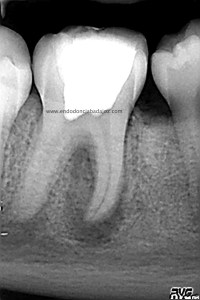

Una vez que hemos limpiado los conductos con un sistema de instrumentación  Protaper en combinación con limas K3. Pasamos a obturar los mismos con una técnica de condensación vertical de ola contínua de Buchanan y un backfilling con la gutapercha inyectada de la pistola ObturaII. Tomamos varias proyecciones, orto-mesio-distal

Con estas tres proyecciones nos quedamos mucho más tranquilos y seguros de un buen sellado hermético y tridimensional des sistema de conductos de esta pieza.